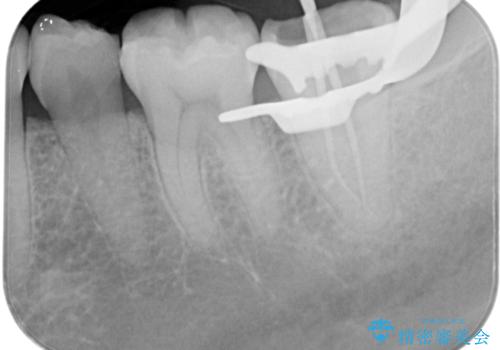

樋状根(といじょうこん)の根管治療

- 昨夜から、寝れないぐらいズキズキ痛む歯があることを主訴に来院されました。

歯髄診にて患歯を特定し、不可逆性歯髄炎の診断のもと治療を行っています。

治療中には過去に修復された材料の下に虫歯を認めましたが、破折線はみとめられませんでした。

治療後すぐに症状は改善され、今後クラウン修復を行う予定です。